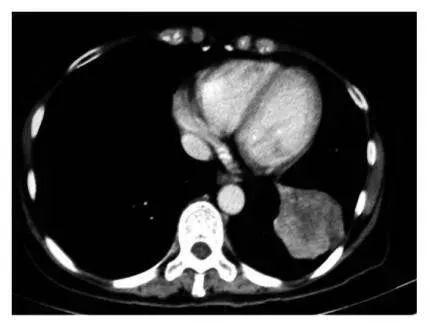

美国晚期肺癌患者慕名前往古巴接受治疗,经疫苗治疗几个月后,肺部影像检查发现肿瘤竟然已经缩小了90%,完全超出了所有人的想象,并且治疗过程完全没有出现化疗时的任何副作用。

癌细胞肿胀坏死的过程

A 治疗前血清 B-D 三个免疫治疗患者的血清